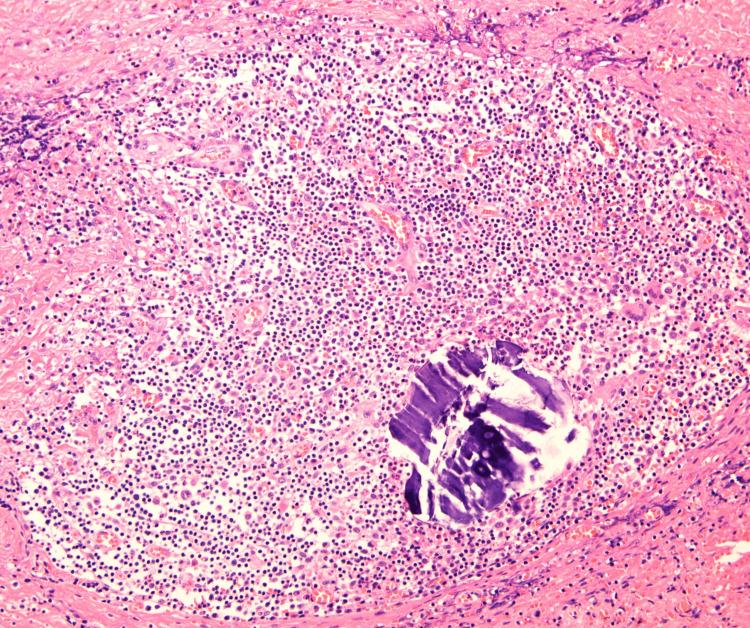

Costochondritis is primarily caused by physical exertion, repetitive movements (such as lifting heavy objects), and severe coughing. Although it is an inflammatory condition, it is not an infection and is often treated with non-steroidal anti-inflammatory drugs (NSAIDs). In contrast, infectious costochondritis usually develops when an infection spreads directly from a postoperative wound or adjacent foci. We present a case of infectious costochondritis with sternal osteomyelitis caused by , where the infection did not spread from adjacent tissues. A 59-year-old man was referred to our hospital with anterior chest pain and swelling persisting for three months. He had been diagnosed with diabetes mellitus three years prior. Three weeks before his visit, a purulent exudate had fistulized into the skin. Two weeks prior, he had sought care from a nearby doctor, who diagnosed a subcutaneous abscess and performed an incision and drainage. Cultures identified . However, the condition did not improve, and chest computed tomography (CT) was performed, showing edema around the seventh costal cartilage, the inferior end of the sternum, and surrounding subcutaneous tissue. Distraction of the seventh costal cartilage was also noted. Magnetic resonance imaging (MRI) with fat-suppressed T2-weighted images showed high intensity in the same area. Blood cultures were negative. Based on these findings, we diagnosed costochondritis and sternal osteomyelitis. Treatment began with oral cefalexin (CEX) for seven days, followed by oral cefcapene pivoxil hydrochloride hydrate (CFPN-PI) for 14 days. During hospitalization, meropenem hydrate (MEPM) was administered. After seven days of MEPM, the seventh costal cartilage and part of the sternum were debrided under general anesthesia. Indicators of the extent of debridement included preoperative MRI, bone cortex hardness under intraoperative palpation, and bone bleeding. MEPM was administered for 14 days, including preoperative treatment, followed by cefepime dihydrochloride hydrate (CFPM) for 14 days and levofloxacin hydrate (LVFX) for seven days. After 11 months of follow-up, there was no recurrence of costochondritis or osteomyelitis. Infectious costochondritis with sternal osteomyelitis caused by was successfully treated with debridement. Properly determining the extent of debridement perioperatively is crucial for effective treatment.

肋软骨炎主要由体力活动、重复性动作(如提重物)和剧烈咳嗽引起。虽然它是一种炎症性疾病,但不是感染性疾病,通常用非甾体抗炎药(NSAIDs)治疗。相比之下,感染性肋软骨炎通常在感染从术后伤口或邻近病灶直接蔓延时发生。我们报告一例由[具体病因未给出]引起的伴有胸骨骨髓炎的感染性肋软骨炎病例,感染并非从邻近组织蔓延而来。一名59岁男性因前胸疼痛和肿胀持续三个月被转诊至我院。他三年前被诊断患有糖尿病。就诊前三周,脓性渗出物形成瘘管通向皮肤。两周前,他曾到附近医生处就诊,医生诊断为皮下脓肿并进行了切开引流。培养结果鉴定出[具体病菌未给出]。然而,病情并未改善,遂进行胸部计算机断层扫描(CT),显示第七肋软骨、胸骨下端及周围皮下组织水肿。还注意到第七肋软骨有分离。脂肪抑制T2加权磁共振成像(MRI)显示同一区域呈高强度信号。血培养结果为阴性。基于这些发现,我们诊断为肋软骨炎和胸骨骨髓炎。治疗开始时口服头孢氨苄(CEX)7天,随后口服头孢丙烯水合物(CFPN-PI)14天。住院期间给予美罗培南水合物(MEPM)。使用MEPM 7天后,在全身麻醉下对第七肋软骨和部分胸骨进行清创。清创范围的指标包括术前MRI、术中触诊时骨皮质硬度以及骨出血情况。MEPM使用14天,包括术前治疗,随后使用头孢吡肟二盐酸盐水合物(CFPM)14天和左氧氟沙星水合物(LVFX)7天。经过11个月的随访,肋软骨炎和骨髓炎均未复发。由[具体病因未给出]引起的伴有胸骨骨髓炎的感染性肋软骨炎通过清创成功治愈。围手术期正确确定清创范围对于有效治疗至关重要。